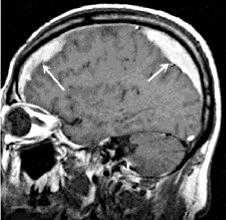

о МРТ-наиболее информативный метод визуализации хронической субдуральной гематомы (хСДГ):

- Хроническая субдуральная гематома (хСДГ) часто имеет гиперинтенсивный сигнал (вследствие наличия метгемоглобина) на Т1-, Т2-, PD-ВИ, а также FLAIR

- МРТ обеспечивает более информативную визуализацию мембраны и тромба:

Утолщение или обширное распространение неомембран или тромба в сочетании с масс-эффектом являются показанием для эвакуации хронической субдуральной гематомы (хСДГ) и мембранэктомии